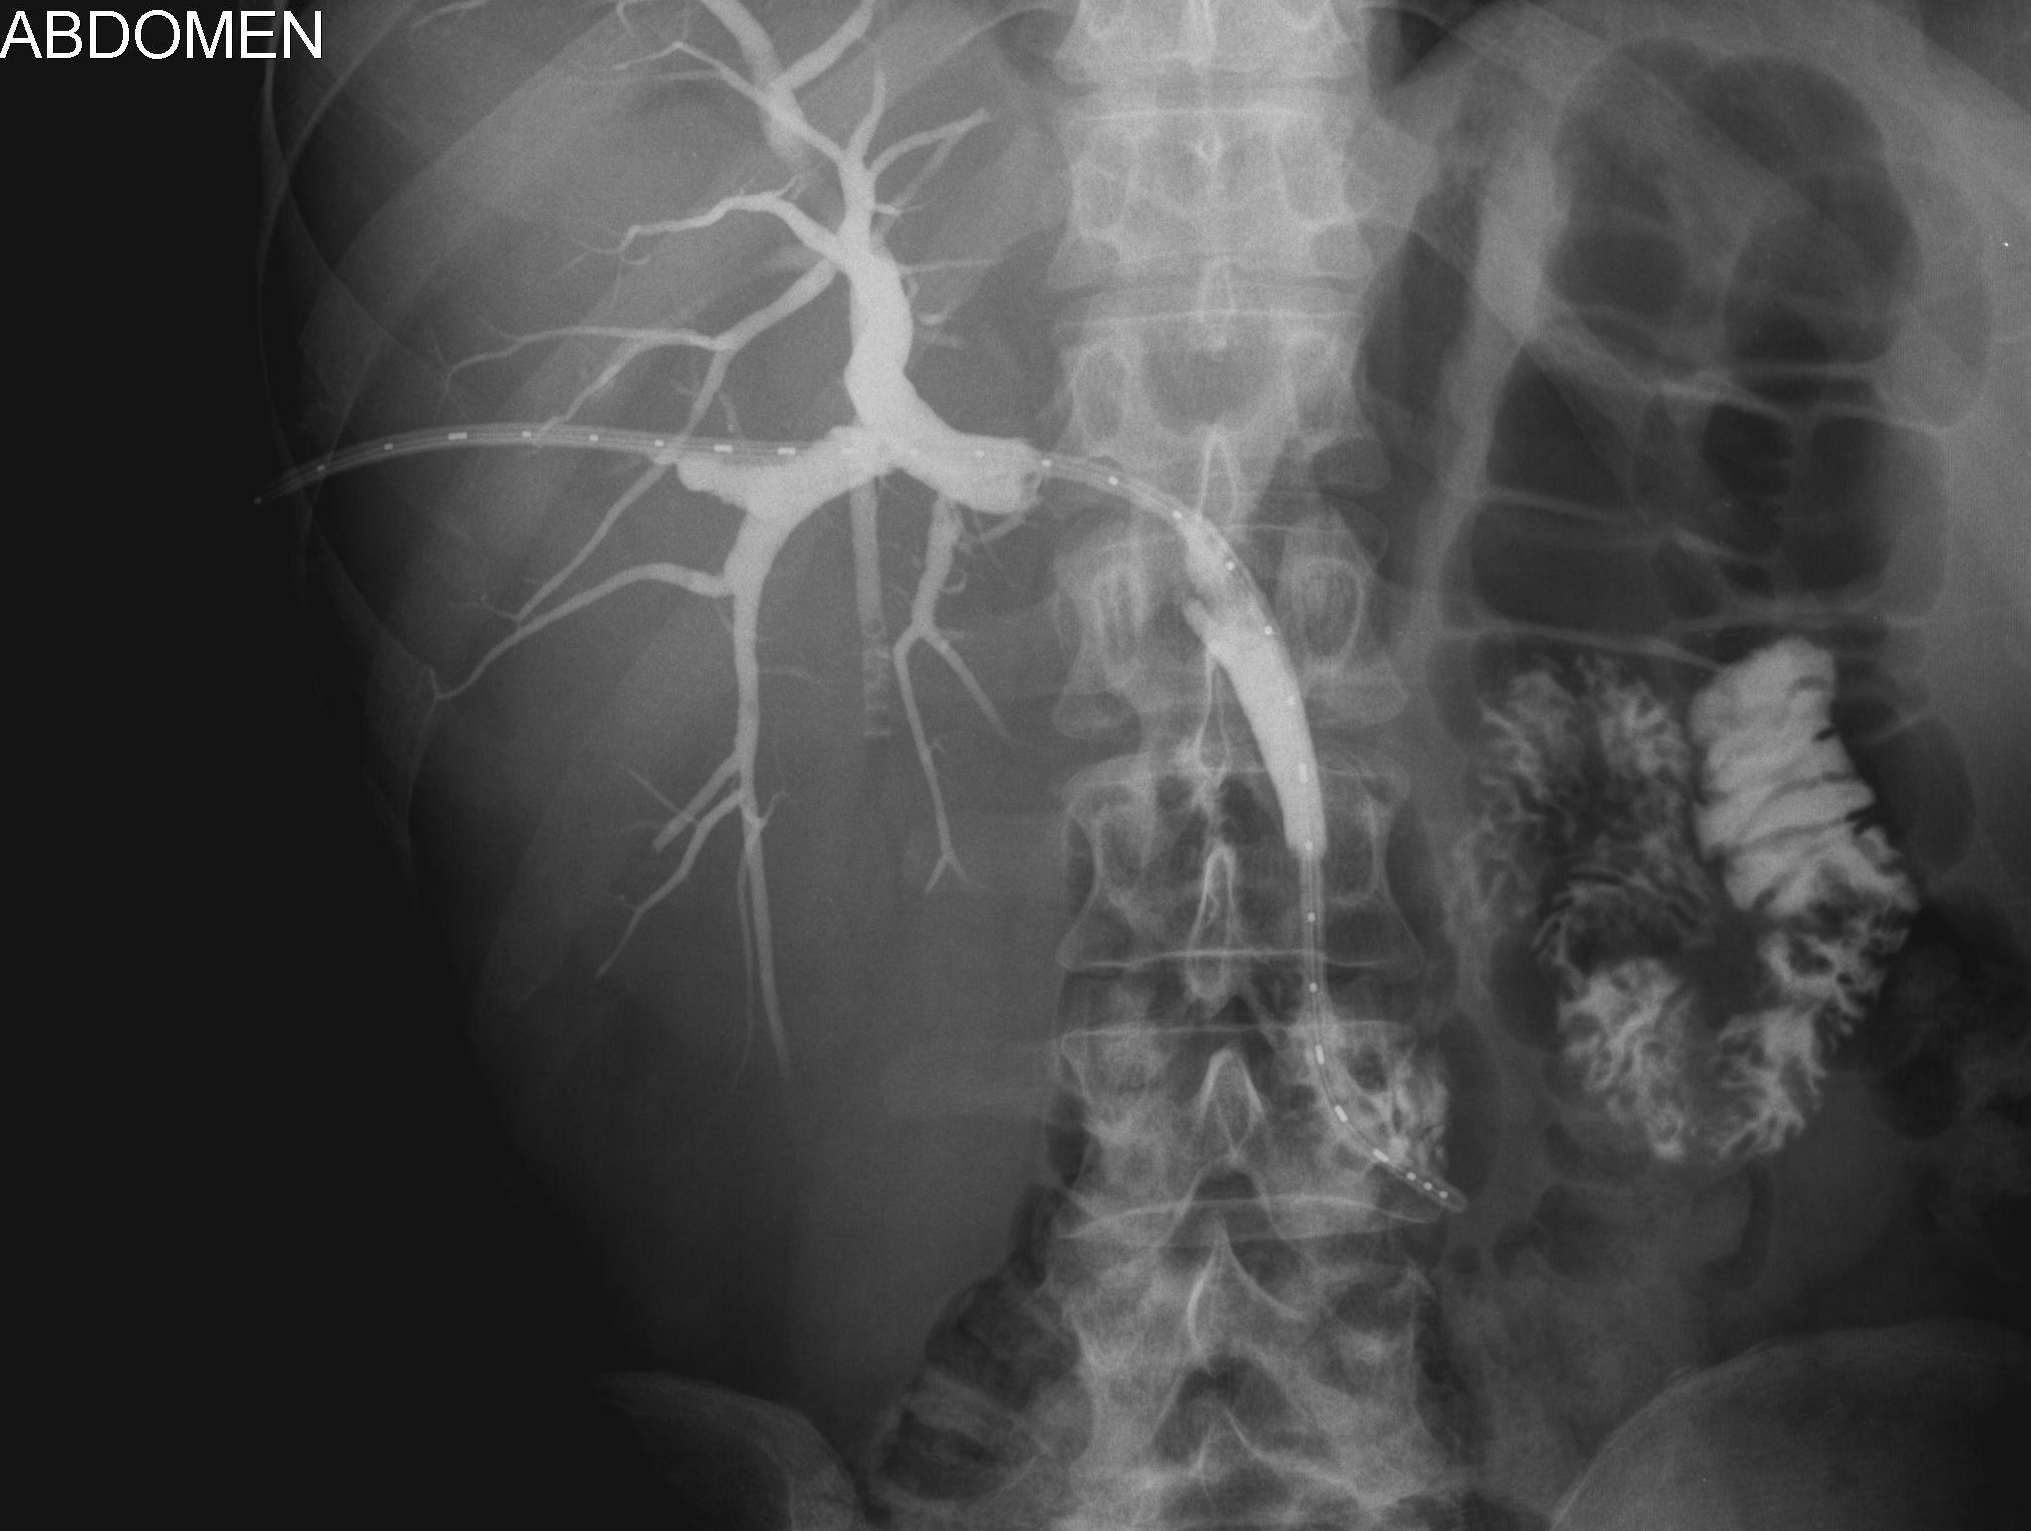

Cholangiografia - widok dróg żółciowych z założonym aplikatorem do brachyterapii (French 5)oraz markerem do planowania